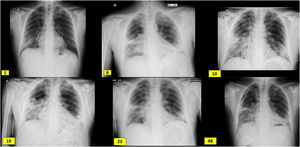

Radiological evolution since admission (day 1), boluses of methylprednisolone (day 6), kidney biopsy (day 10), initiation of tocilizumab (day 19), initiation of rituximab (day 23) and hospital discharge (day 48). It shows subpleural peripheral reticular thickening of the middle fields, right basal field and lingula and interstitial alveolar opacities in the middle and lower fields of the right lung and lower fields of the left lung.

Case descriptionA 60-year-old male from Ecuador who was admitted in August 2020 due to few days of dyspnea, without any other referred symptoms. Upon arrival, he was normotensive and afebrile with basal oxygen saturation greater than 94%, but tachypneic at 16 breaths per minute. SARS-CoV-2 RT-PCR in pharyngeal exudate was positive. Laboratory results revealed usual parameters of COVID infection with a clear renal involvement: Plasma creatinine 3.94 mg/dl, eGFR (CKD-EPI): 16 ml/min/1.73 m2, microhematuria and moderate proteinuria (Table 1). Chest X-ray with bilateral interstitial pneumonia (Fig. 1). The patient worked as a painter in construction, had no toxic habits or contact with animals, and had long-term hypertension.